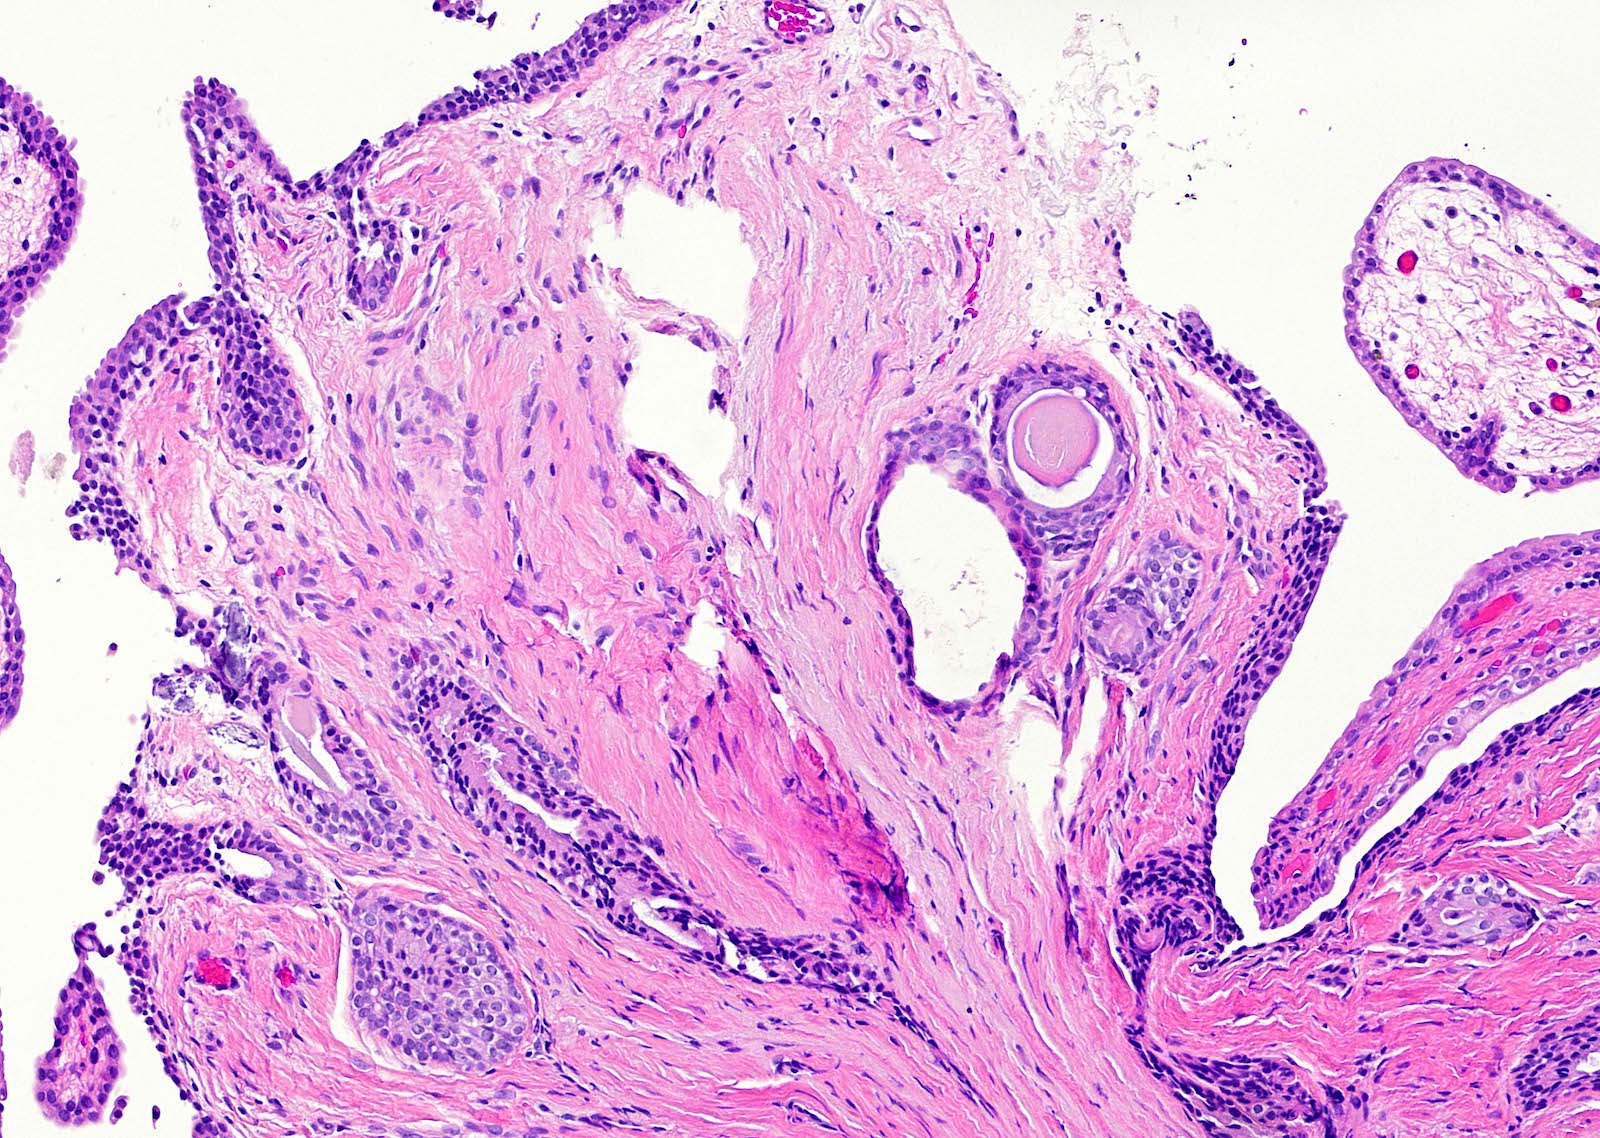

- Fibroepithelial urethral polyp (Am J Surg Pathol 2005;29:460):

- Pattern 1: most common pattern includes the following features

- Broad cloverleaf-like and club-like projections covered by normal urothelium and composed of dense fibrovascular stroma with florid cytitis cystica et glandularis (most common morphologic variant)

- Back to back glands present in the stalk

- Anastomosing nests of benign urothelial cells resembling inverted papilloma

- Dilated cysts with intracystic papillary contents

- Degenerative reactive atypia of stromal cells

- Pattern 2: numerous small papillae with dense fibrous cores and areas of glandular differentiation

- Pattern 3: urothelial lined broad edematous papillae mimicking polypoid urethritis; urothelial lined broad fibrous papillae with subepithelial edema

Microscopic (histologic) images

Contributed by Y. Albert Yeh, M.D., Ph.D.

Fibroepithelial polyp